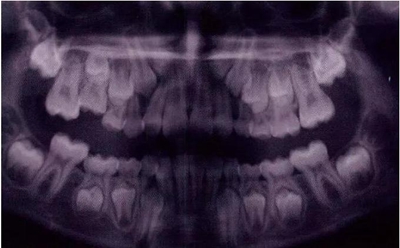

X線片還會顯示合平面呈現出一個臺階,并通常會有一個角度朝向固連牙的角型牙槽骨缺損。(圖5)。許多臨床醫(yī)生更愿意選擇拍攝曲面體層片而不是根尖片,因為考慮到乳牙下沉經常會雙側發(fā)生并合并其它發(fā)育異常,同時也為了確定是否需要正畸治療。臨床檢查和影像學檢查聯(lián)合評估同樣也為了排除其它病因,譬如原發(fā)性的萌出障礙,牙齒嵌入或者其它異常。

圖5:由于乳牙下沉而導致合平面發(fā)生改變的曲面體層像

圖11是一張曲面體層片,上面顯示了一名九歲男孩同時患有55,75,和85的下沉。其55和85 為中度下沉,75為輕度下沉。這幾顆牙都沒有齲齒,都伴有恒牙胚的存在,并且沒有鄰牙傾斜和間隙喪失的臨床表現。給予這個孩子的方案是醫(yī)囑三個月常規(guī)復診以觀察監(jiān)測這些牙的下沉情況。結果這些牙均未加重至超過中度下沉,并且全部自然脫落,恒牙正常萌出。

圖11:曲面體層片顯示一名9歲男孩乳磨牙下沉,繼承恒牙胚存在。